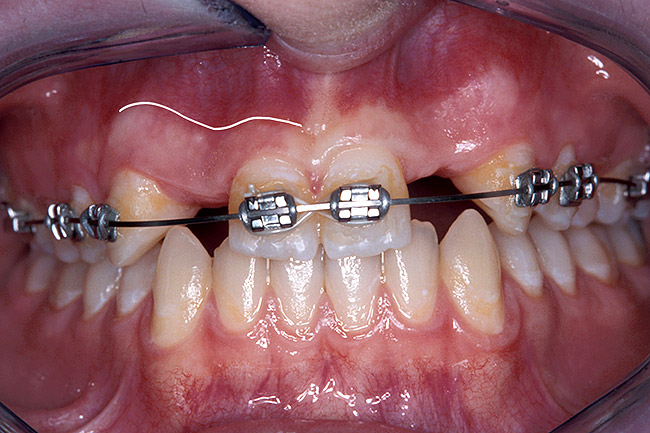

A 17-year-old boy presented with a history of congenitally missing maxillary lateral incisors. The patient had been under the care of an orthodontist for several years to manage his occlusion during his adolescent growth phase. The patient originally presented with his parents after being told that the “braces were ready to be removed, and their son was now ready for implants to replace the missing teeth.” This is not an u.common circumstance, and unfortunately the orthodontic alignment was performed before the patient was sent to the restoring dentist. Therefore, the orthodontist was not aware of the space requirements for future implant placement. This case highlights the importance of proper.communication between all members of the implant team, especially during the orthodontic planning phase. The patient’s medical history was unremarkable, and the patient was found to be healthy and a good potential candidate for dental implants to replace the missing lateral incisors.

Periapical radiographs were taken to help determine the mesial-distal inclinations of the adjacent tooth roots (Figure 1). The radiographs revealed a serious issue, convergent roots for the right canine and right central, which eliminated that area as a potential implant-receptor site. The space between the left central and canine teeth was minimal, although the roots were relatively parallel. Clinical examination (manual palpation of the root eminences superiorly to the vestibule on the right side) confirmed the root convergence (Figure 2A). The flat, wide zone of the keratinized tissue and lack of interdental papilla was evident for the missing right lateral incisor. There was a marked difference in clinical appearance for the left lateral, which could impact the eventual plan of treatment (Figure 2B). Other significant clinical findings included bilateral facial bone concavities, which existed as a result of the congenitally missing tooth roots. As a diagnostic cue to the underlying bone topography, it is important to follow the demarcation between attached and unattached gingival tissue, and note the crestal width of the available keratinized tissue (Figure 2C).

Figure 2a  Pretreatment buccal views showed (A) root convergence, (B) a difference in clinical appearance of the left lateral, and (C) significant crestal width of keratinized tissue.

Figure 2a

Figure 2b  Pretreatment buccal views showed (A) root convergence, (B) a difference in clinical appearance of the left lateral, and (C) significant crestal width of keratinized tissue.

Figure 2b

Figure 2c  Pretreatment buccal views showed (A) root convergence, (B) a difference in clinical appearance of the left lateral, and (C) significant crestal width of keratinized tissue.

Figure 2c